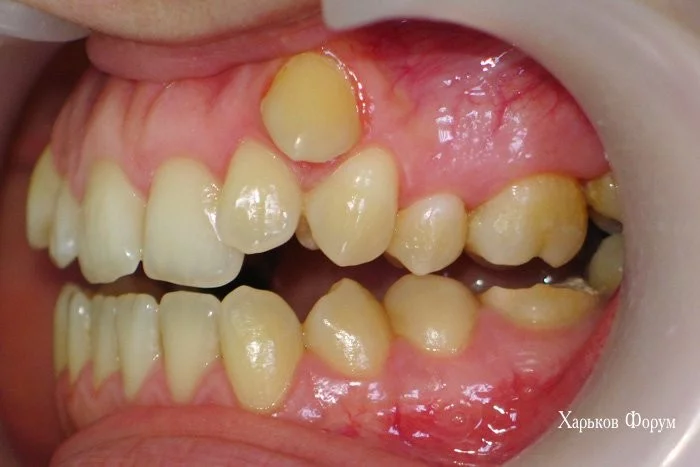

ФОТО прилагаем

На фото виден значительный прогресс даже не тренированному глазу.

Я еще раз приложу снимки зубов ДО и ПОСЛЕ.

3. У Вас есть скученное положение зубов и дефицит места более 7 мм. А это железобетонное показание для лечения с удалением. Вы зря не взяли модели челюстей ДО лечения, для своего нового доктора! Они бы ему пригодились. Возможно, будут полезны фото